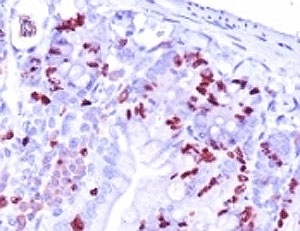

IHC analysis of formalin-fixed, paraffin-embedded mouse small intestine stained with BrdU antibody (clone BRD.3).

It reacts with Bromodeoxyuridine (BrdU) in single stranded DNA (produced by partial denaturation of double stranded DNA), BrdU coupled to a protein carrier, as well as free BrdU. BrdU is a thymidine analog, incorporated into cell nuclei during DNA synthesis prior to mitosis. Antibody to BrdU is helpful in detecting S-phase cells, providing useful information on the aggressiveness of tumors.